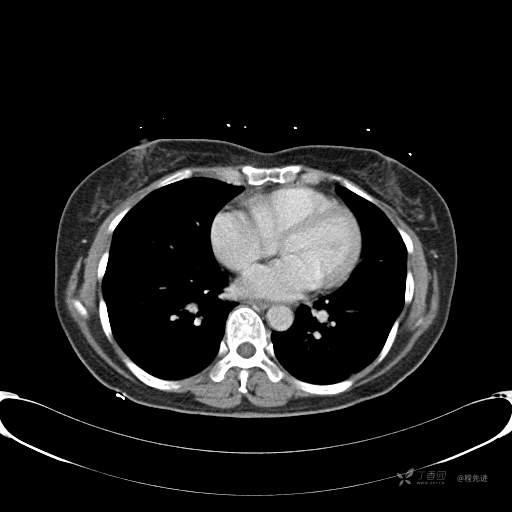

患者性别:女

患者年龄:57岁

简要病史:体检发现

CT增强

平扫CT值约40HU(未上传图像),增强后动脉期CT值约70HU,静脉期CT值约97HU。

肺硬化性血管瘤 (20)